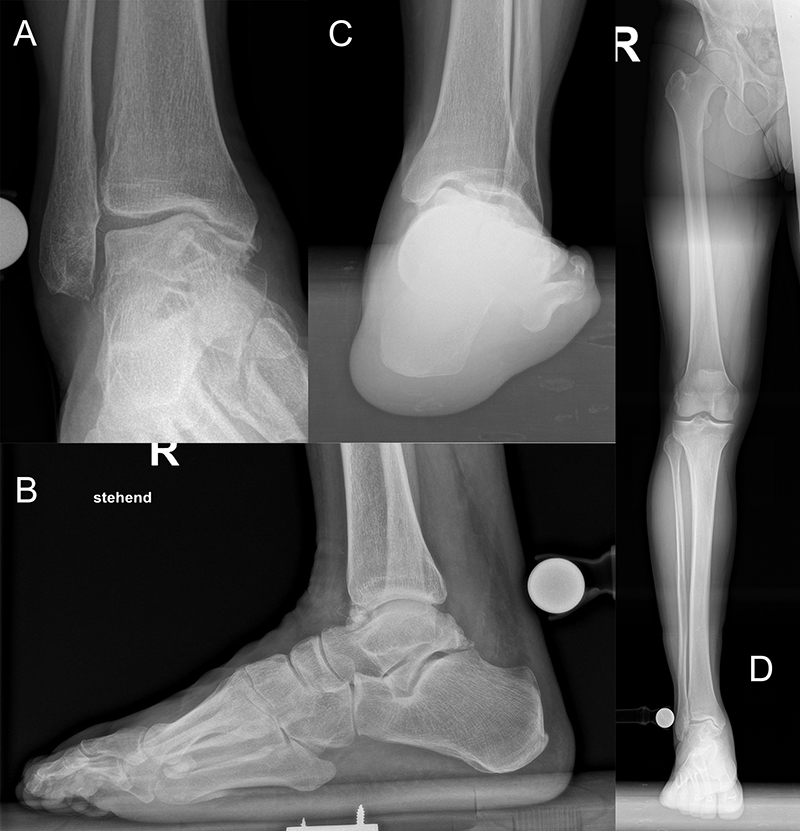

Native Röntgenaufnahmen des Sprunggelenks in 2 Ebenen unter Belastung (antero-posterior und lateral) erlauben Gelenkspaltverschmälerung, osteophytäre Anbauten sowie Achsfehlstellungen zu beurteilen. Eine „Canale-Aufnahme“ (Pronation des Fußes von ca. 15 °, Röntgenstrahl 75 ° nach kranial) 9 kann hilfreich sein, die subchondralen Oberflächen einzusehen. Die korrekte Abbildung der Sprunggelenkgabel in der sogenannten „Gabel-Aufnahme“ (mortise-view) ist zudem notwendig zur Beurteilung der Gelenkkongruenz. An Grenzen stößt die konventionelle Röntgenaufnahme allerdings bei OCLs ohne weitere knöcherne Veränderungen. Bis zu 50% der OCLs sind auf konventionellen Röntgenaufnahmen nicht sichtbar. Auch kann der Zustand des Knorpels nicht beurteilt werden 10. Bei Achsfehlstellungen werden zusätzlich Rückfußachs-Aufnahmen (Saltzman View) angefertigt bzw. eine Einbeinstandaufnahme zur Bestimmung der Becken-Bein-Achse.

Zur Vollansicht und zum Lesen der Bildbeschreibung bitte das Bild anklicken.

In den letzten Jahren hat die digitale Volumen Tomografie (DVT) erheblich an Bedeutung gewonnen. Der Vorteil dieses Verfahrens ist eine computertomografieartige Abbildung unter Vollbelastung des Fußes mit der Möglichkeit einer 3-D Rekonstruktion. Verglichen zur Computertomografie hat die DVT eine deutlich geringere Strahlenbelastung 12. Aus dem Datensatz lassen sich Projektionsbilder errechnen, sodass viele belastete konventionelle Aufnahmen durch eine DVT überflüssig werden.